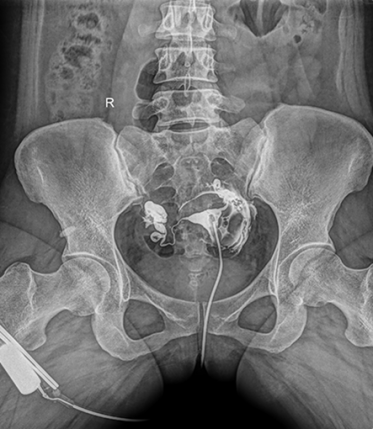

多功能動(dòng)態(tài)平板DR,采用U型臂結(jié)構(gòu),具有靜態(tài)DR攝影、數(shù)字透視、數(shù)字造影和可視化攝影的功能。

電動(dòng)旋轉(zhuǎn)內(nèi)平衡結(jié)構(gòu),可實(shí)現(xiàn)快捷擺位,滿(mǎn)足特殊體位的靜態(tài)與動(dòng)態(tài)檢查。